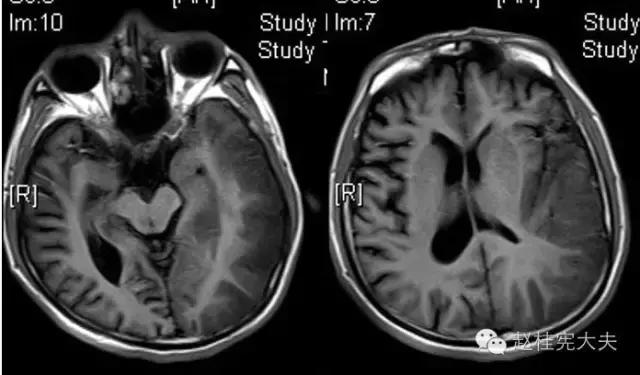

完善检查,头颅MRI回报:左侧颞顶枕叶急性梗死灶。

当看到磁共振片子的时候,我知道,我们忽略了一些东西......

患者的磁共振影像不符合脑血管病的血供分布,跨了大脑中动脉和大脑后动脉范围,且病灶偏皮层分布。大脑前、中、后动脉血供分布(横断面)见下图

这不是一个真的“脑卒中”,而是一个“卒中样发作”。